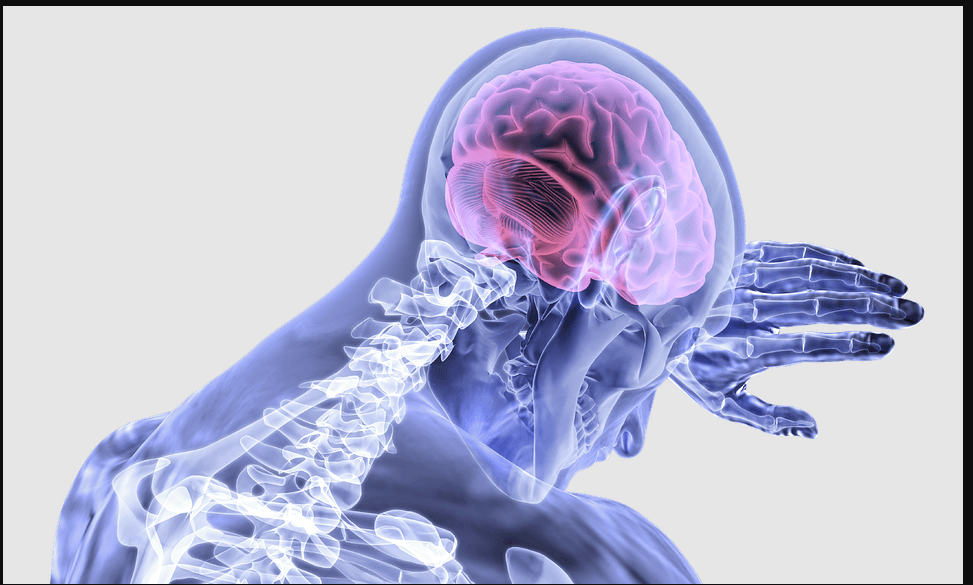

Golpes en la cabeza: Conocé si pueden provocar un ACV

El médico neurólogo jefe de la Unidad de ACV del Hospital Padilla, Jerónimo Cossio, habló sobre las potenciales consecuencias que pueden tener los golpes en la cabeza a nivel de la salud cerebro vascular.

En este contexto, Cossio advirtió que los traumatismos crónicos reiterados, de leve intensidad incluso, tienen su consecuencia a largo plazo y que se denomina encefalopatía traumática crónica: “Esta es una enfermedad neurológica crónica y degenerativa, eso significa que progresivamente neuronas se van perdiendo a consecuencia de golpes traumatismos reiterados a lo largo de la vida del paciente, sobre todo conocido en deportes de mucho contacto, como el boxeo, el rugby o el fútbol americano”.

Respecto a las consecuencias el especialista refirió que suelen empezar a notarse años o incluso décadas después de los eventos traumáticos reiterados, con manifestaciones clínicas especialmente desde el punto de vista cognitivo, como trastornos de memoria, de atención, dificultad para resolver problemas, trastornos de la conducta, del comportamiento, de estado de ánimo, ansiedad, depresión y hasta incluso pueden acontecer trastornos motores, como parkinsonismo.

“No vinculamos al ACV con traumatismos crónicos reiterados a lo largo de la vida del paciente. En cuanto a los golpes en la cabeza que pueden acontecer cuando se viaja en un vehículo sin protección, como un casco, son perjudiciales y el ACV como consecuencia de un traumatismo de cráneo de este tipo, puede tener lugar. Esto también puede acontecer ante un movimiento brusco del cuello que pueda lesionar arterias y producir lo que se llama disección arterial”, explicó.